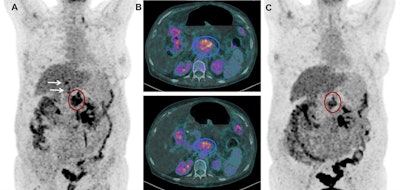

For the study, six patients with confirmed metastatic ductal pancreatic adenocarcinoma received Lu-177 3BP-227 as salvage therapy. They underwent scintigraphy and SPECT/CT to assess tumor uptake and eligibility for treatment. Based on the patient's condition, FDG-PET/CT was performed eight to 12 weeks after therapy to determine treatment efficacy (JNM, May 2018, Vol. 59:5, pp. 809-814).

Lu-177 3BP-227 was well-tolerated by the patients, the researchers found. In addition, one patient experienced significant improvement of symptoms and quality of life, surviving 13 months from diagnosis and 11 months from the start of therapy with Lu-177 3BP-227. The five-year survival rate for patients with this type of cancer is less than 5%.